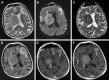

Background: Secondary central nervous system lymphoma (SCNSL) is a rare and aggressive disease, which is defined as secondary central nervous system (CNS) involvement in patients with systemic lymphoma. According to previous reports, SCNSL presents mostly with leptomeningeal spread; however, our experience differs. In the present study, we demonstrate the diversity of magnetic resonance imaging (MRI) patterns in SCNSL.

Patients and methods: Initial morphological MRI findings in 21 patients (10 women and 11 men with mean age 62.3±16.2 years) with SCNSL were retrospectively evaluated. All patients suffered from neurological symptoms and underwent MRI, and all cases were histologically verified. Twelve patients were treated by corticosteroids at the time of the initial MRI.

Results: Parenchymal lesions were present in 18 of 21 cases (85.7%), solitary meningeal infiltration was present in 1 patient (4.8%), leptomeningeal infiltration in combination with hypophyseal involvement in 1 patient (4.8%), and solitary involvement of the sixth cranial nerve (CN) was found in 1 patient (4.8%). Multiple lesions were present in 11 of 21 cases (52.4%). Diffusion restriction in all or part of the lesion was detected in 14 of 18 cases (77.8%). All parenchymal lesions had an infiltrative appearance and most enhanced homogenously (11 of 17 cases; 64.7%). A combination of parenchymal and meningeal involvement was found in 10 of 21 cases (47.6%). Infiltration of the CNs, basal ganglia, corpus callosum, and ependyma was present in 8 of 21 cases (38.1%) for each of the abovementioned structures; hypothalamic-hypophyseal axis was affected in 7 of 21 cases (33.3%).

Conclusion: In contrast to previous reports, SCNSL presented as parenchymal disease. MRI is not sufficient for differentiation between primary and secondary CNS lymphoma.